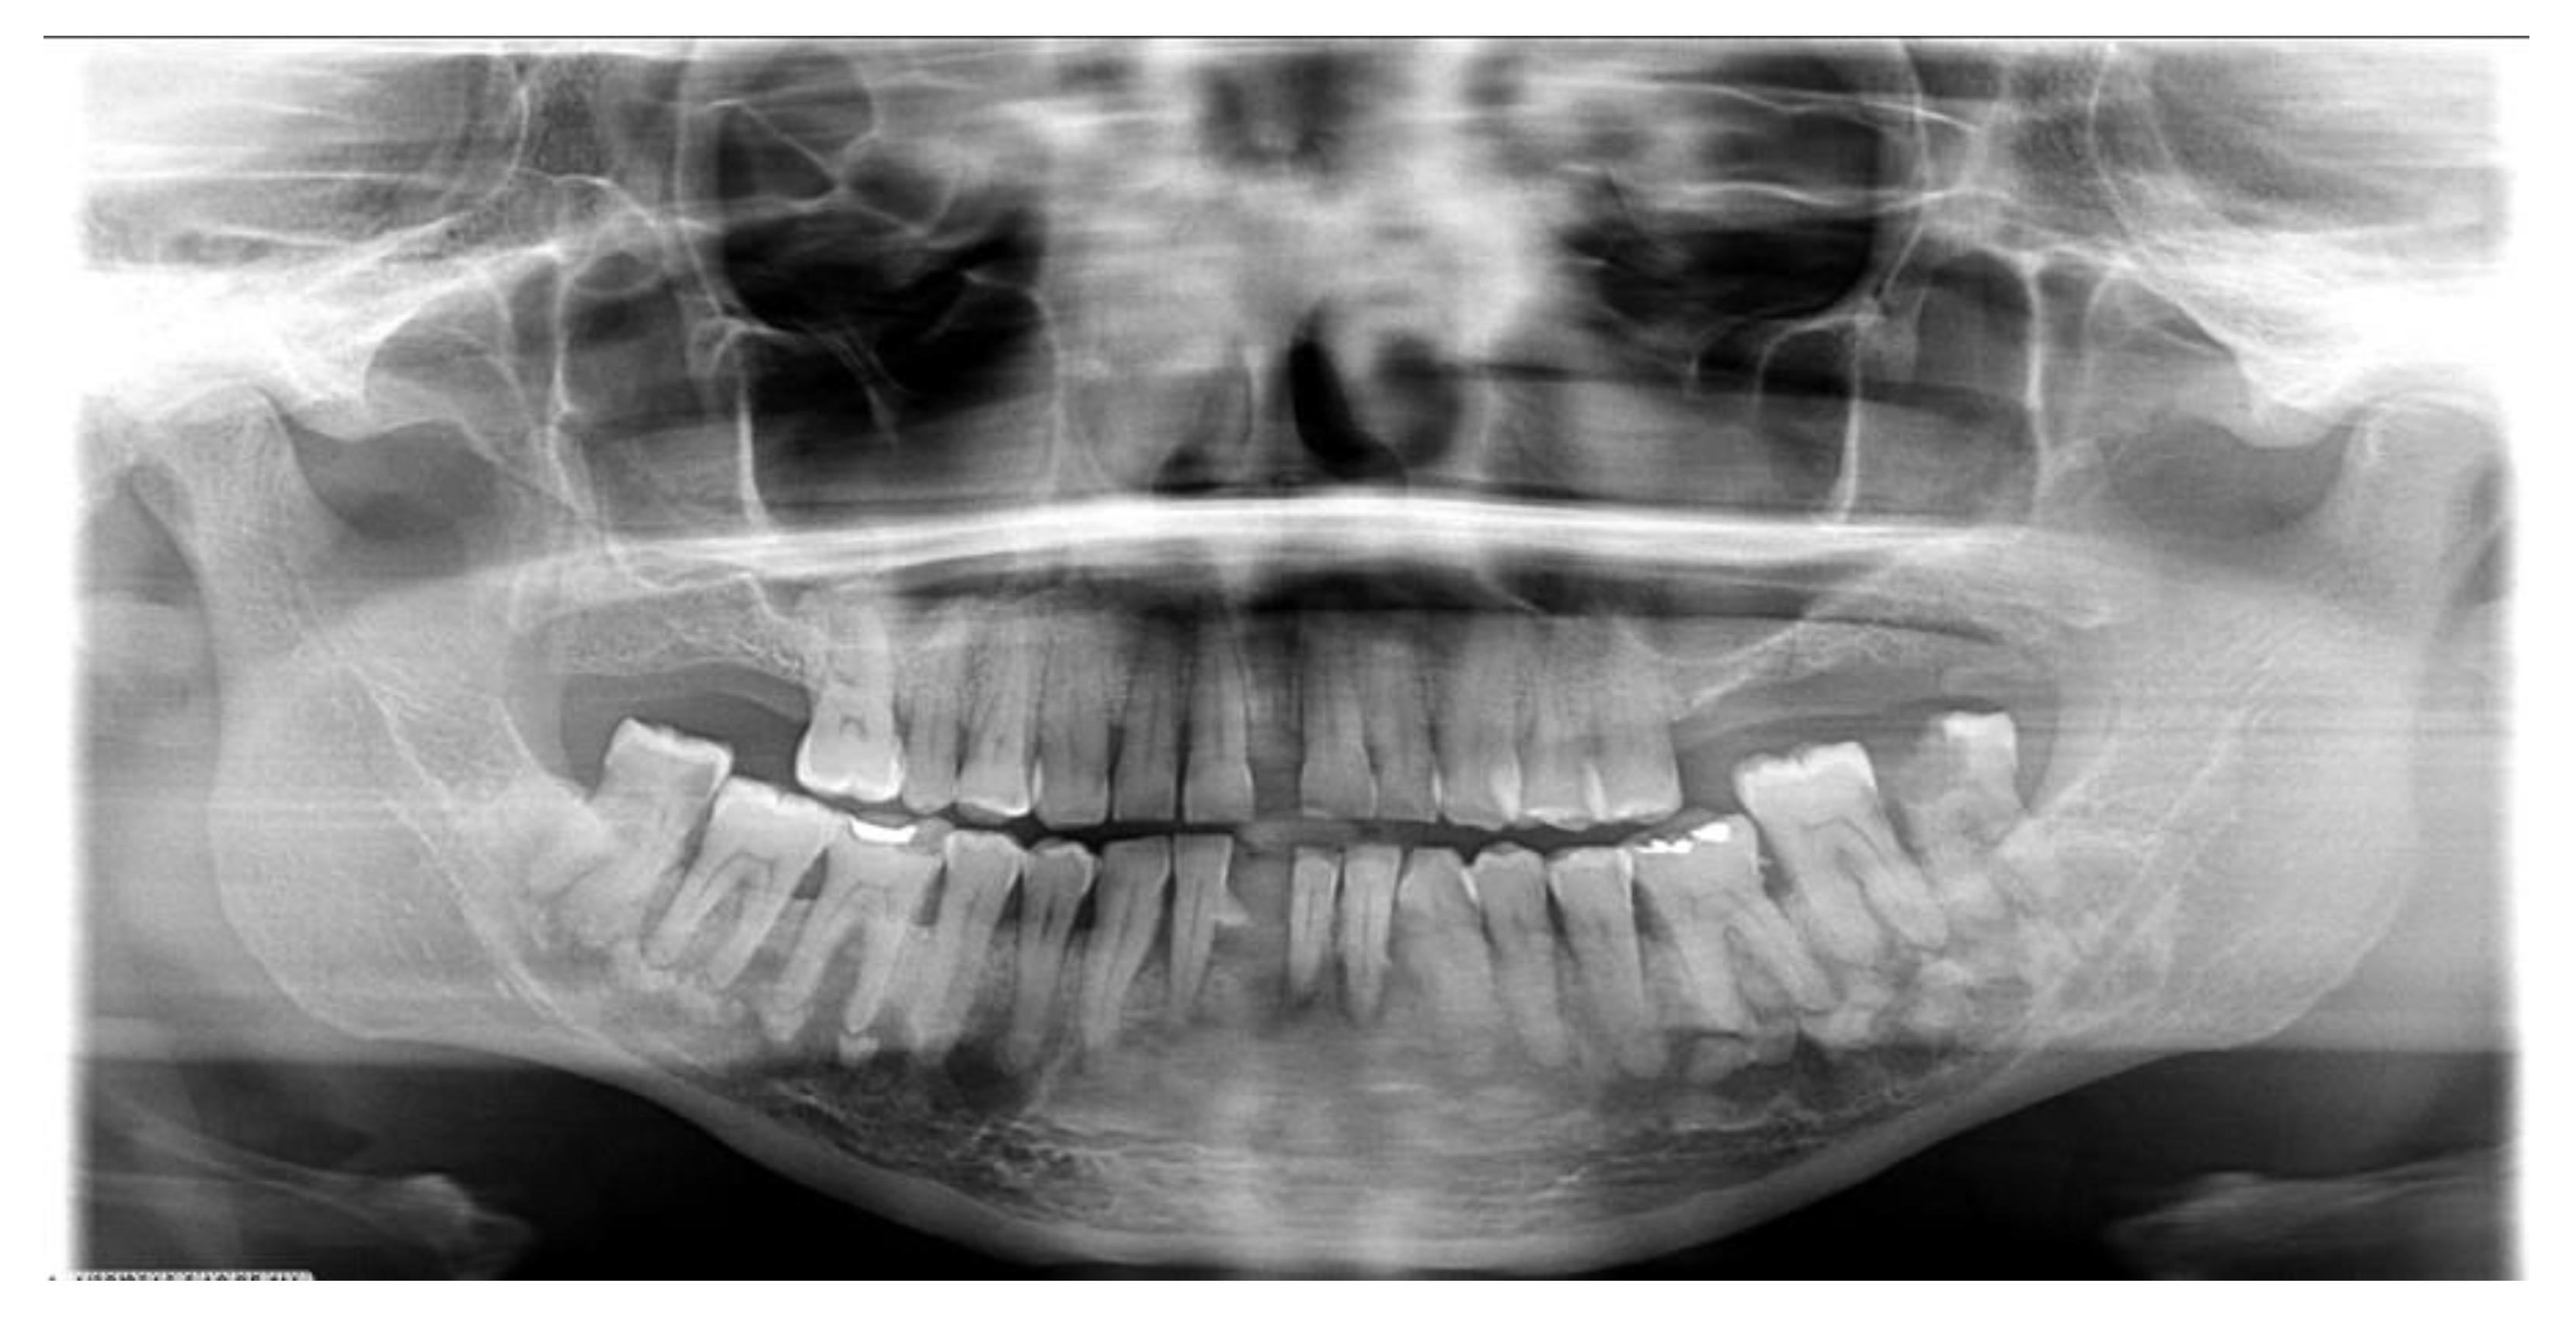

Types of COD